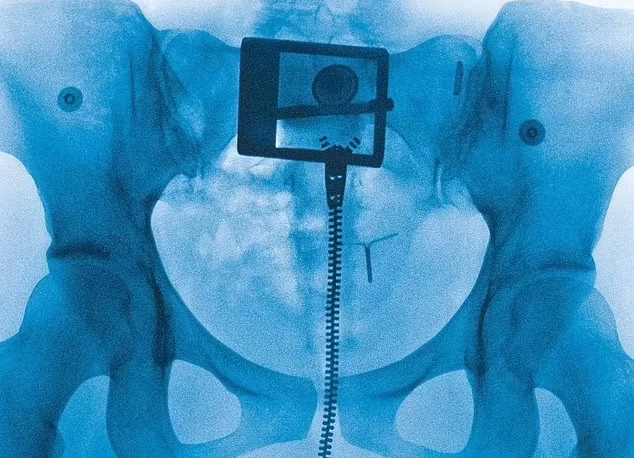

Para "Virgin", Lorde escolheu produtores que trabalham com nomes como Charli XCX e Olivia Rodrigo, a dupla Jim-E Stack e Dan Nigro. Ela também optou como capa a imagem de um raio-x da região pélvica, de alguém usando jeans e com um Dispositivo Intrauterino (DIU), método contraceptivo inserido diretamente no útero. Um outro detalhe sobre chamou atenção dos que adquiririam o disco: no encarte de fotos, Lorde colocou uma foto em close da sua genitália, enquanto veste uma calça transparente de plástico.